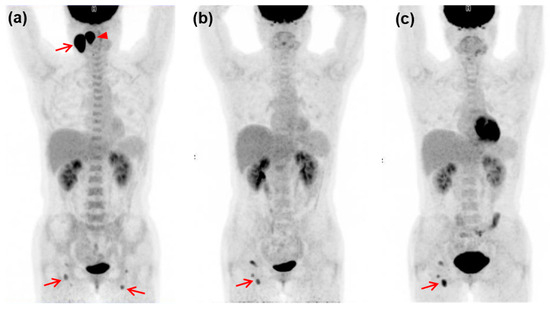

3.2. Assessment of FDG PET/CT